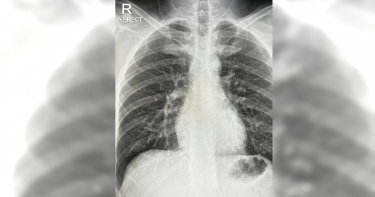

打完三劑後確診「還是咳不停」 他一照X光驚:肺部都是傷疤

馬來西亞一名男子伊沙克(Sharmine Ishak),過去曾接種3劑新冠疫苗,但上月底卻仍確診了新冠肺炎,即便已經解隔,還是咳嗽咳不停,且咳嗽情況還越來越糟。他於本月19日接受X光檢查,才發現這場染疫的狂咳,已經讓他的肺部出現了傷疤。今年30多歲的伊沙克,是正值身體狀況良好的青壯年階段,去年因為防疫,他曾在5、7月,共接種2劑AZ疫苗,去年12月又接種了輝瑞的追加針劑。他提到:「大家都說,這個組合效力增強25倍,但我可能遇到更強大的病毒才會染疫」,他還猜測,自己可能是感染到Delta病毒。伊沙克說,他染疫後一直有劇烈咳嗽的症狀,咳嗽從濕咳漸漸變成乾咳,他還分享了自己肺部「滿是傷痕」的X光照,有感而發的說,雖然他沒有惡化到,變成胸膜炎(Pleurisy)等重症,但一直狂咳實在也夠折騰他了,「我無法想像,沒有接種疫苗的人(染疫後)會變怎樣。」